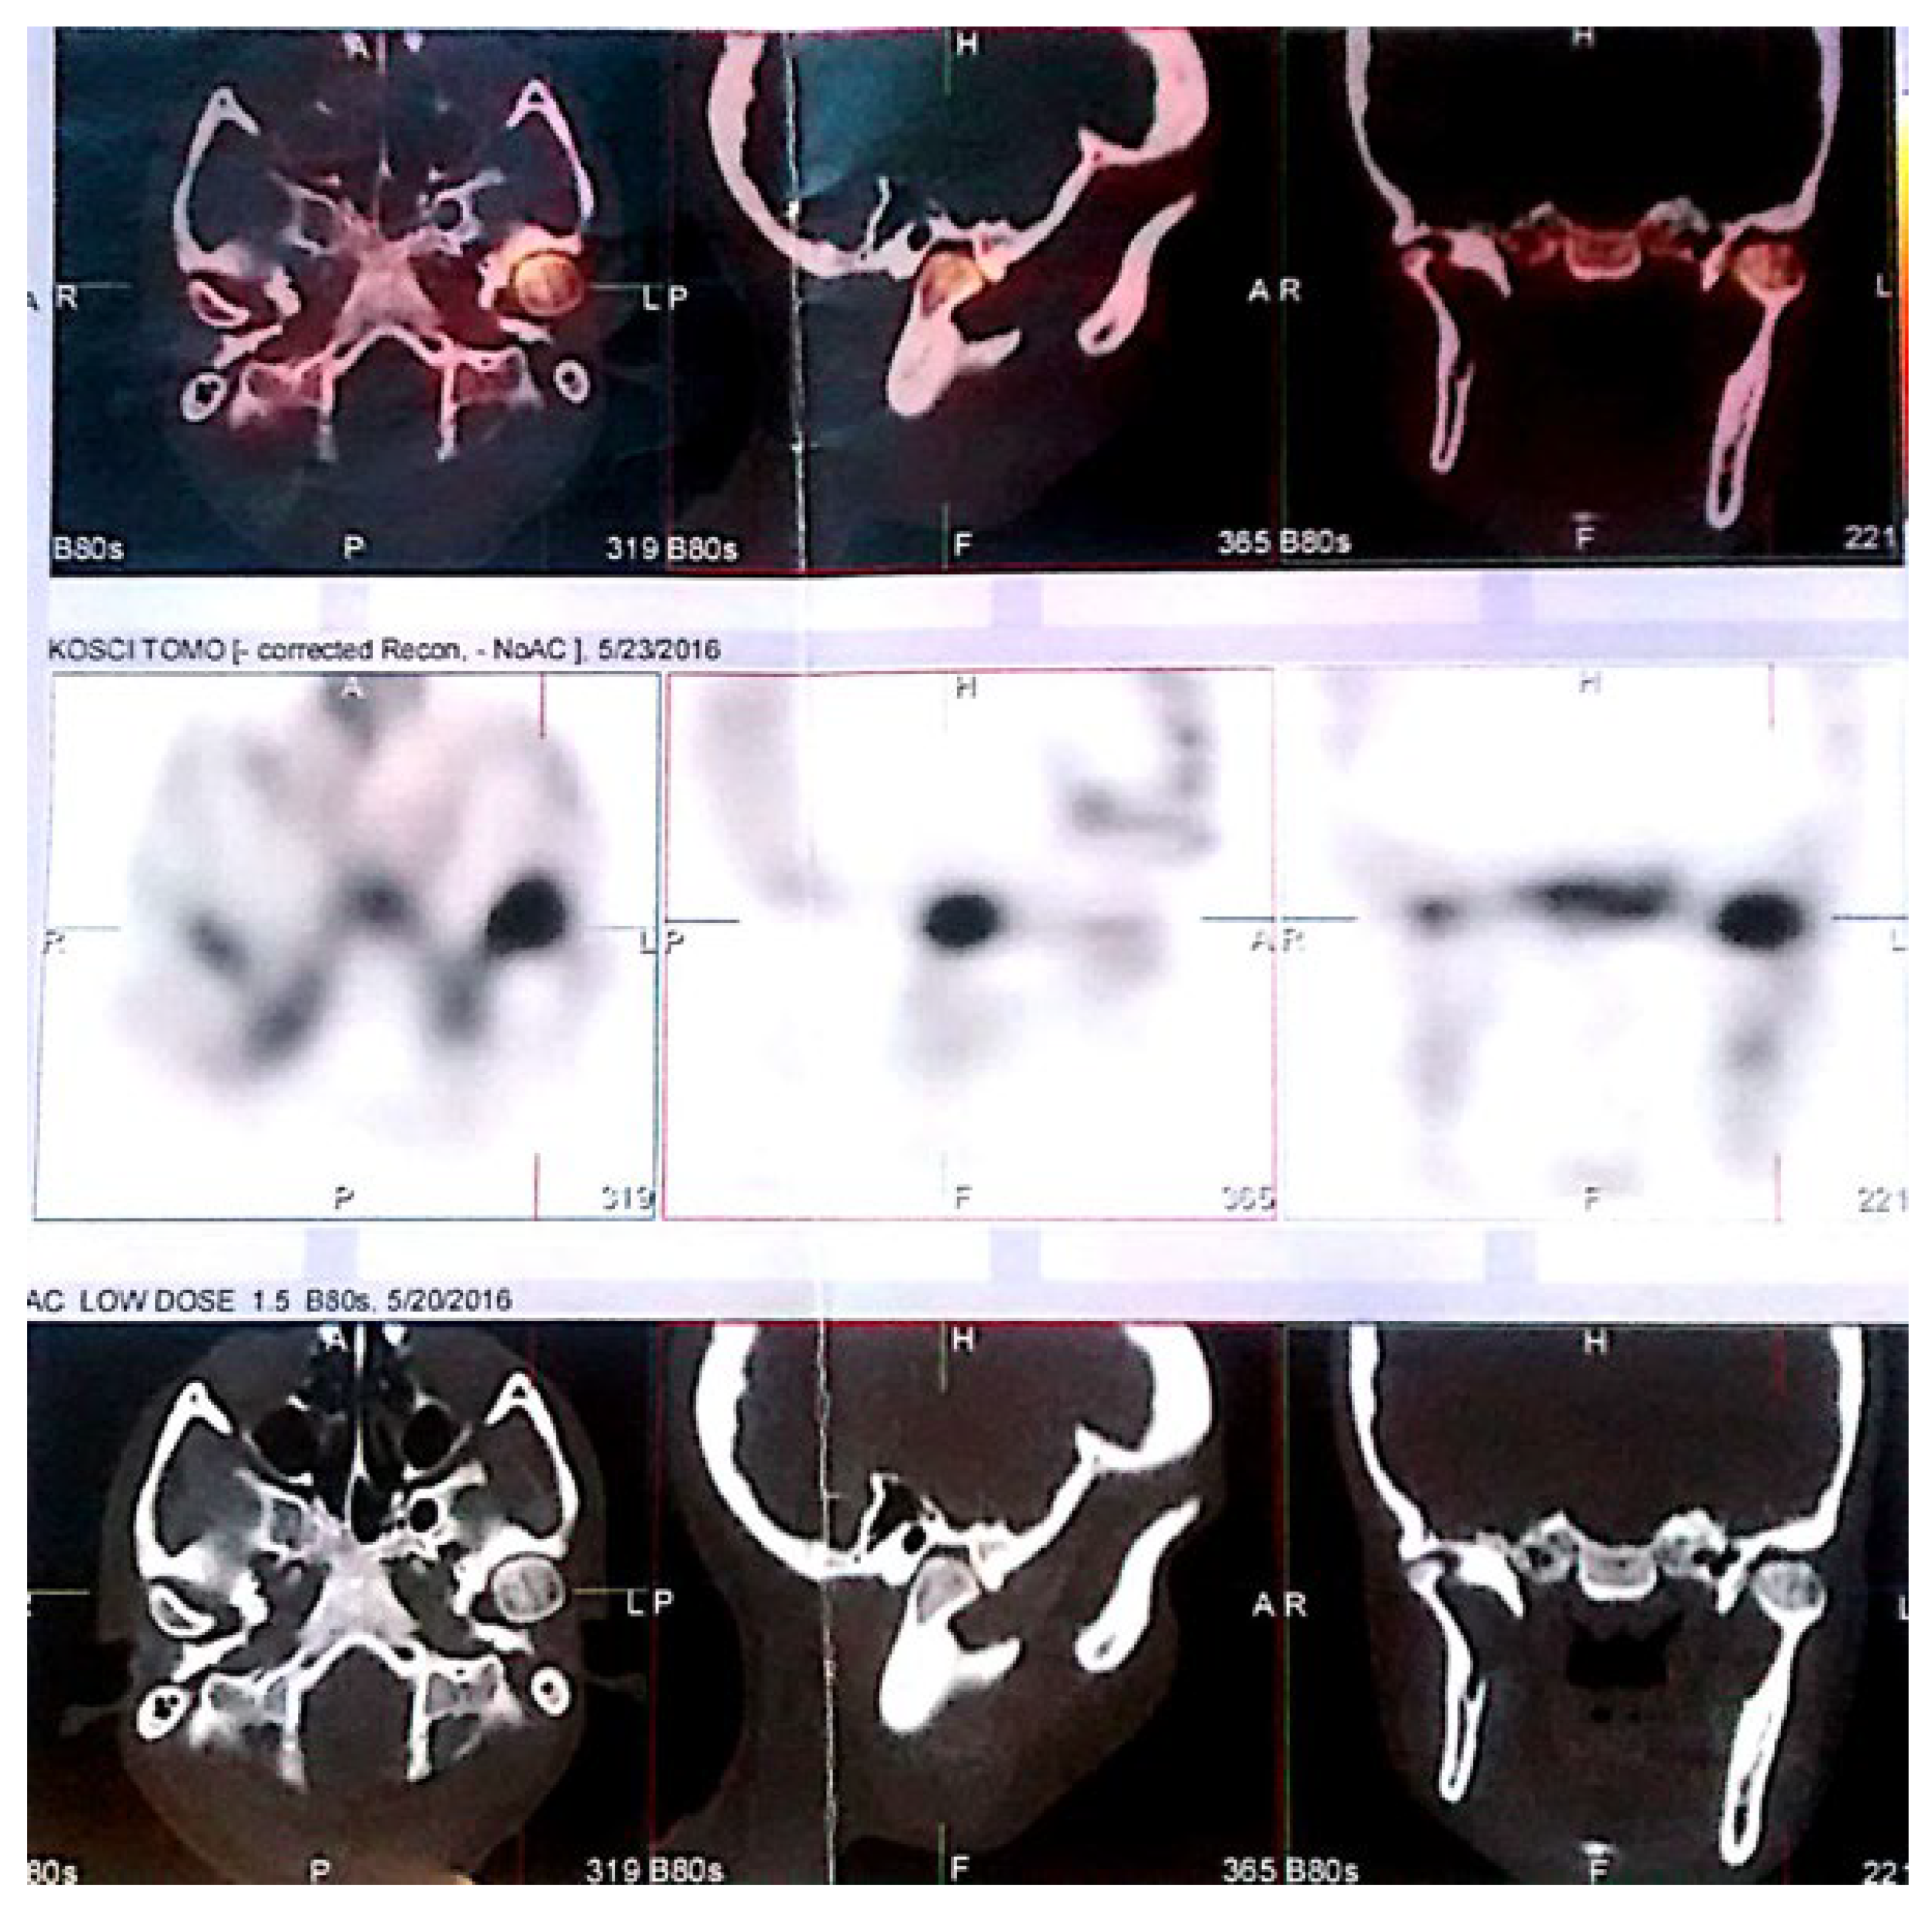

5.2. Scintigraphy and Growth Activity